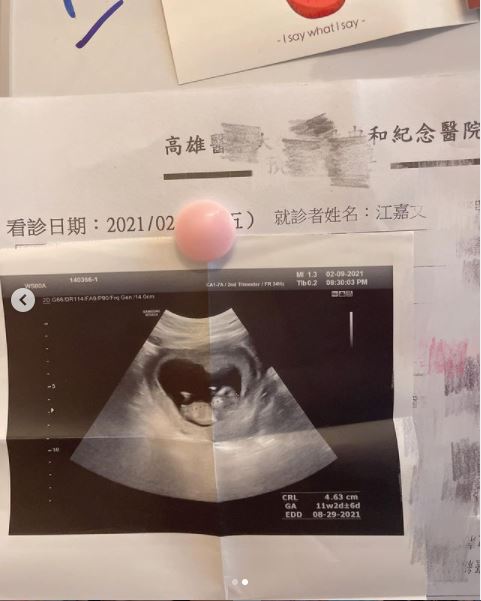

高层次超音波照片能清楚看到许多细节

包含脑部、颜面、心脏、四肢等等,为子宫里的小孩做一个「完整的结构评估」,而高层次超音波异常结构的检出率,大约有八成,每次平均的检查时间约需要30-50分钟。